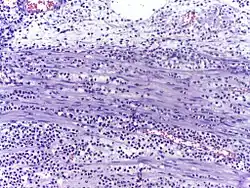

![]() |

Fibroblasts | Fibroblasts in intestinal pneumonia | Category: Fibroblasts | Fibroblast |